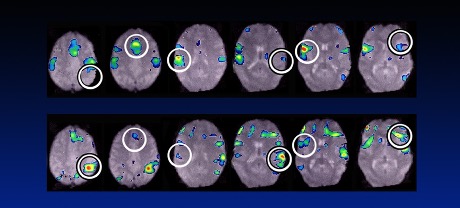

Effects of Trauma and Abuse on the Brain: Before and After Treatment

By Douglas Drossman, MD Content Warning: physical and sexual abuse, trauma Back in the 1980s, a patient came to me, a 12-year-old girl, who would inspire my research and ultimately change the way we understand the link between pain and trauma. Like many of my GI...